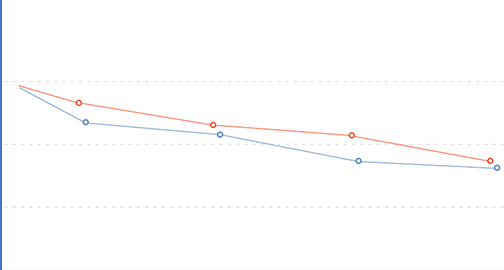

Biologicky aktívna formula pre kĺby zabraňuje chirurgickému zákroku a prispieva k efektívnej rehabilitácii doma.

Zloženie Vasaxal vám umožňuje znížiť dávku nesteroidných protizápalových liekov, ktoré postupne poškodzujú vnútorné orgány. Vasaxal je účinný a bezpečný pre dlhodobé použitie.